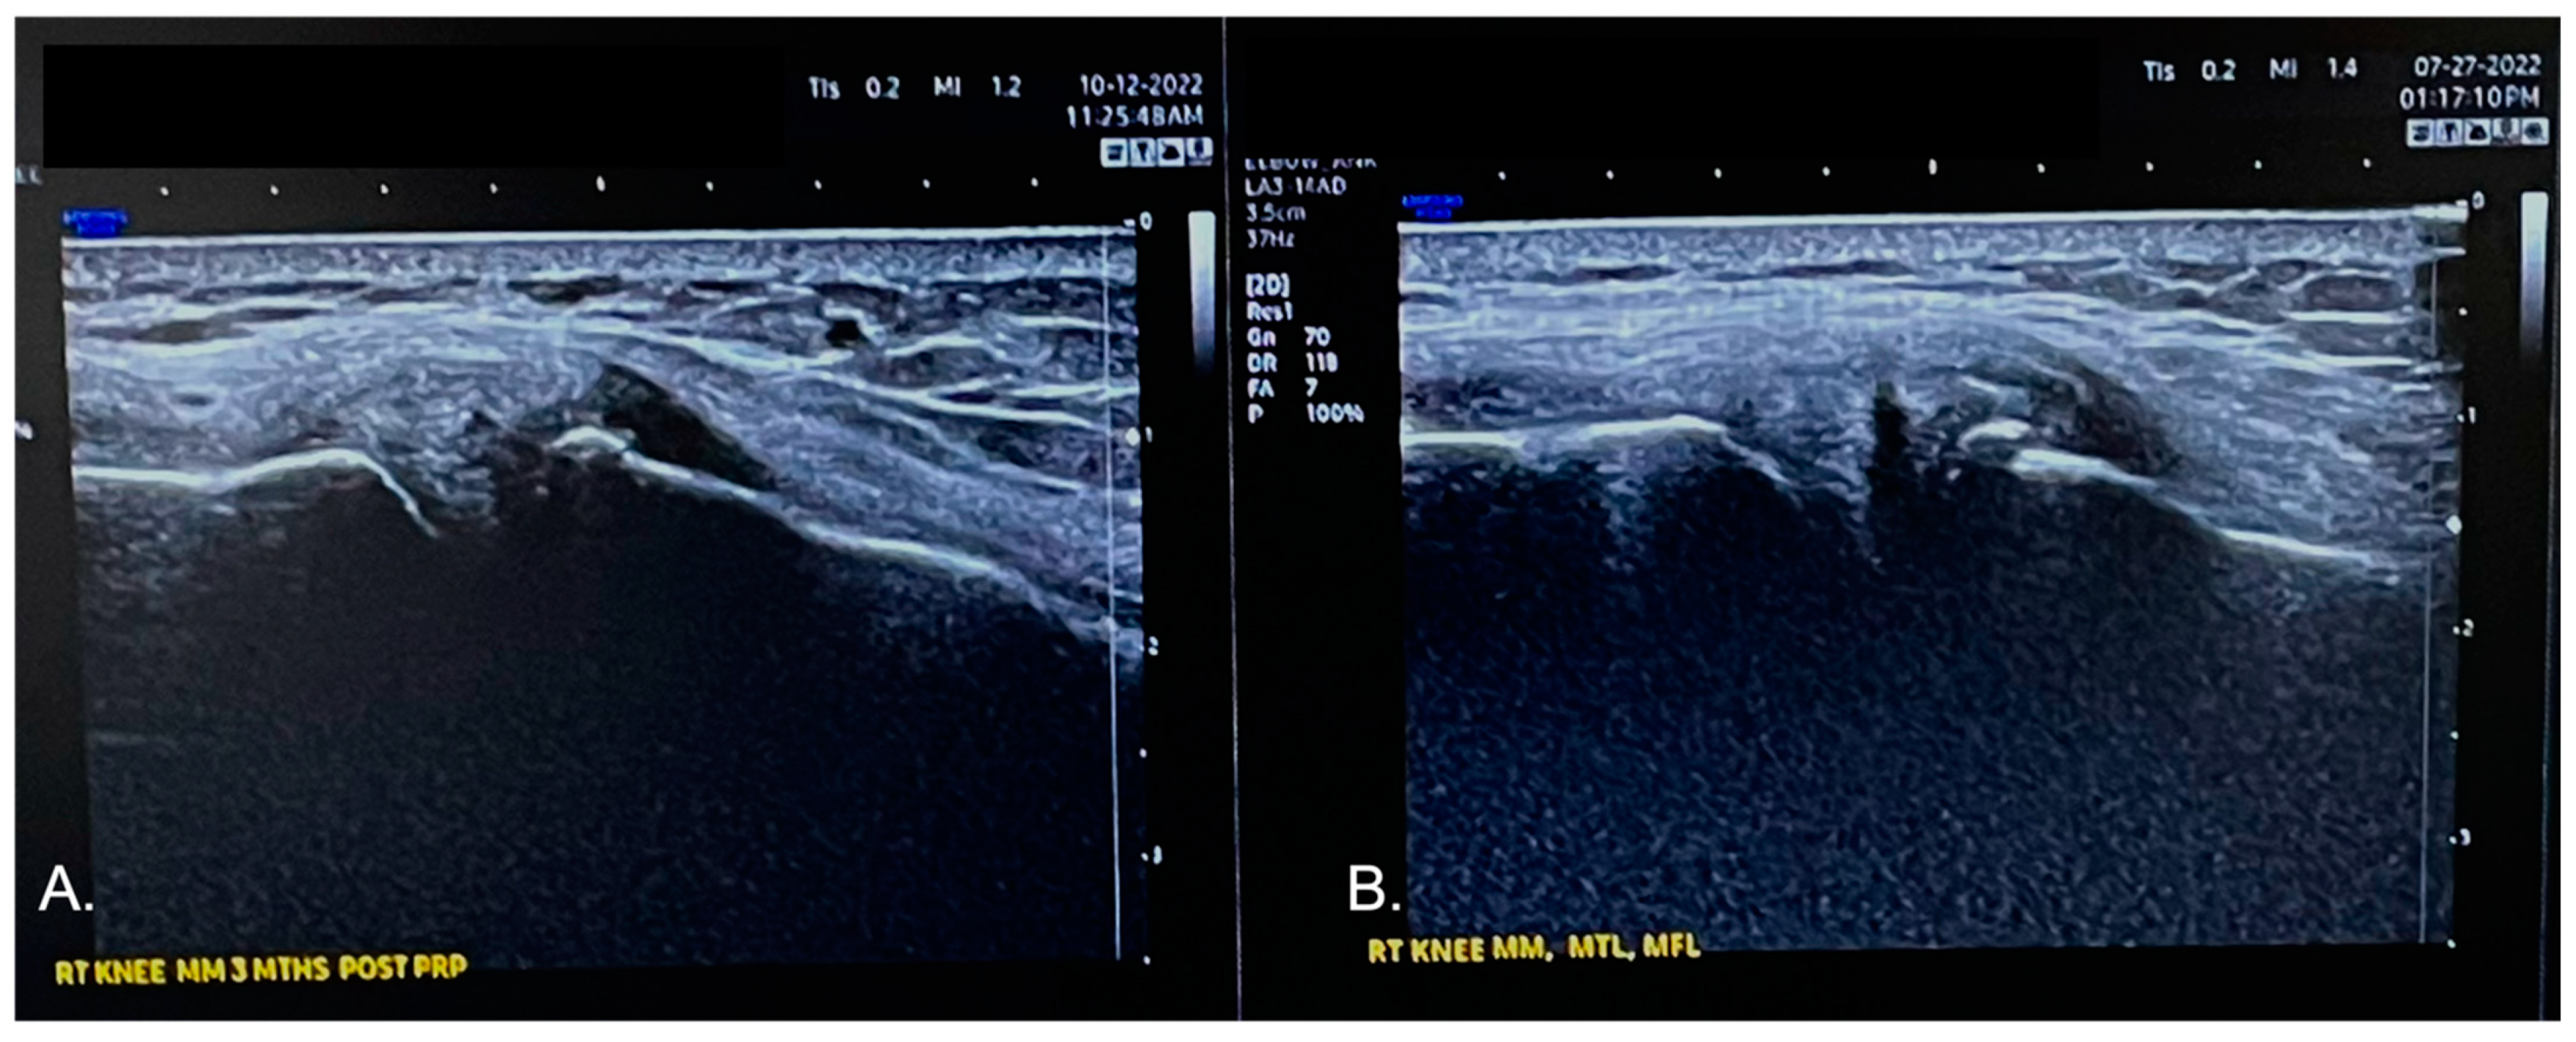

Just prior to submitting this manuscript, at 11 weeks post treatment the right knee was re-evaluated by the same provider (L.P.) using the same ultrasound device. In Figure 5, a comparison image is shown from the medial meniscus and MCL. In 5A, a re-evaluation image is shown: the anechoic defect affecting the red and red/white zone of the meniscus, as noted on the ultrasound image in 5B, is barely visible; this is compatible with a tissue regenerative repair process of the meniscus tear following NR-PRP administration in the meniscus and the femoral and tibial meniscus ligaments. Furthermore, the International Knee Documentation Committee (IKDC) score and the Knee Injury and Osteoarthritis Score (KOOS) improved. At 11 weeks post treatment, both scores increased, 48% and 53%, respectively. The visual analog scale for pain decreased from 6 to 0 in the same period.